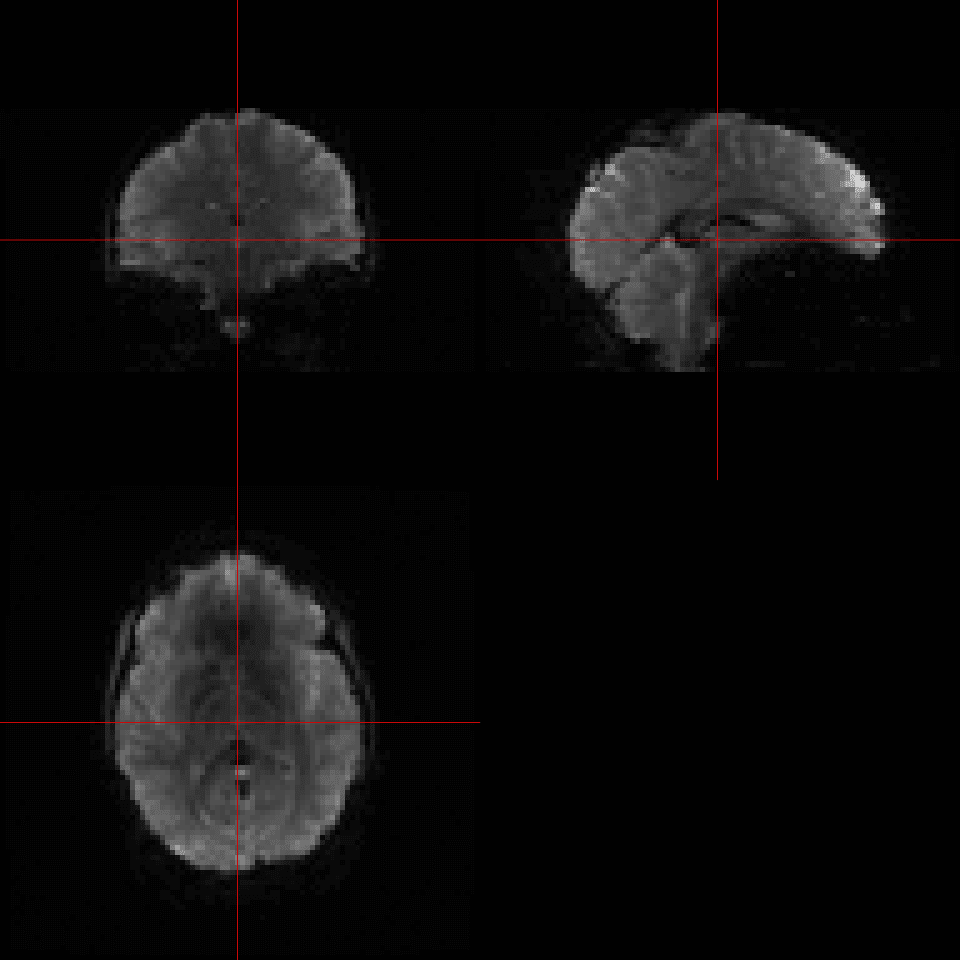

The first attempt at reading this file on line #2 fails. The error message is very informative, bytes 129-132 do not contain the characters DICM which is part of the DICOM Standard. So... it's safe to assume that this file is not a valid DICOM file. Delving further we turn on the debugging option (line #4) and are able to see what the first 128 bytes, which are skipped by default as part of the DICOM Standard, look like. They obviously contain information. By setting skipFirst128=FALSE and DICM=FALSE (line #13) we can override the default settings are start reading information from the first set of bytes. This does the trick and with the debugging option turned on every field from the header is displayed. No errors have occurred, so we can display the image data from this file (line #40) below.